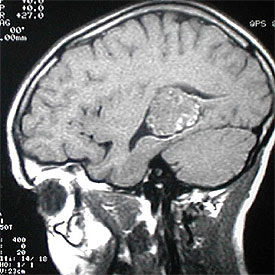

Los angiomas cavernosos, que afectan al 0,5% de la población, causan pequeñas hemorragias y lesiones neurológicas

Dos años han transcurrido desde que M. L., mujer de 50 años afincada en Madrid y con una vitalidad extraordinaria, acusó los primeros síntomas de un angioma cavernoso o cavernoma. Lo característico de esta malformación congénita de los vasos sanguíneos cerebrales es que el llamado lecho capilar (los vasos más pequeños) tiende a romperse generando ataques epilépticos o hemorragias cerebrales.

Este trastorno, del que todavía se desconocen muchas facetas, afecta al 0,5% de la población general y constituye el 15% de las malformaciones vasculares cerebrales. La mayor parte de los cavernomas son asintomáticos y se diagnostican por casualidad cuando se realiza una resonancia magnética. La única opción terapéutica es la cirugía, que, salvo casos graves o de difícil acceso, ofrece un porcentaje de éxito cercano al 95%.

El cavernoma puede aparecer en cualquier zona del cerebro y sus síntomas dependen de su localización y de cómo afecte a sus zonas cercanas. Se establecen dos grandes grupos: esporádicos, en los que aparece un único angioma, y múltiples, cuando aparecen varios en una misma persona. Aproximadamente una quinta parte de los angiomas cavernosos son múltiples y dentro de éstos hay un grupo importante de origen genético o familiar.

"Esta anomalía vascular, que se caracteriza por la presencia de vasos capilares anómalos, tanto en el tamaño como en la forma de la pared capilar, no contiene células cerebrales. El problema radica en que ese lecho capilar anormal tiene cierta tendencia a romperse y a producir pequeñas hemorragias que irritan el cerebro vecino. Dichas hemorragias pueden originar dos efectos principales: ataques epilépticos y hemorragias más grandes que, a su vez, pueden provocar lesiones neurológicas que afecten a ciertas funciones cerebrales", afirma Julio Albisua Sánchez, médico adjunto del servicio de Neurocirugía de la Fundación Jiménez Díaz de Madrid.

Este experto explica que ciertos ictus hemorrágicos son la expresión de algunos angiomas cavernosos y que sólo cuando se realiza la resonancia magnética se detecta la malformación del lecho capilar.